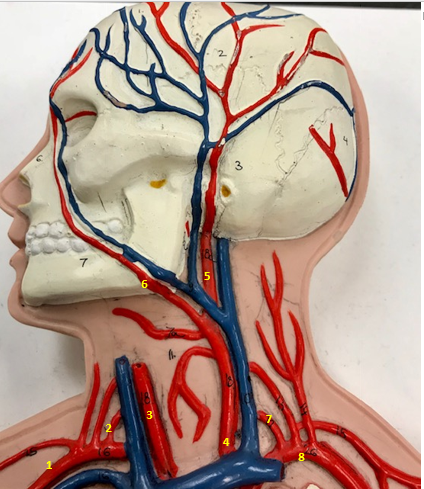

Right subclavian artery

Name #1

Supplies blood to right arm and shoulder

Function of right subclavian artery (1)

Right vertebral artery

Name #2

Supplies blood to brain and spinal cord

Function of right vertebral artery (2)

Right common carotid artery

Name #3

Supplies blood to right neck and head

Function of right common carotid artery (3)

Left common carotid artery

Name #4

Supplies blood to left neck and head

Function of left common carotid artery (4)

Left external carotid artery

Name #5

Supplies blood to face neck and skull

Function left external carotid artery (5)

Left facial artery

Name #6

Supplies blood to face and neck

Function of left facial artery (6)

Left vertebral artery

Name #7

Supplies blood to brain and spinal cord

Function of left vertebral artery (7)

Left subclavian artery

Name #8

Supplies blood to left arm and shoulder

Function of left subclavian artery (8)